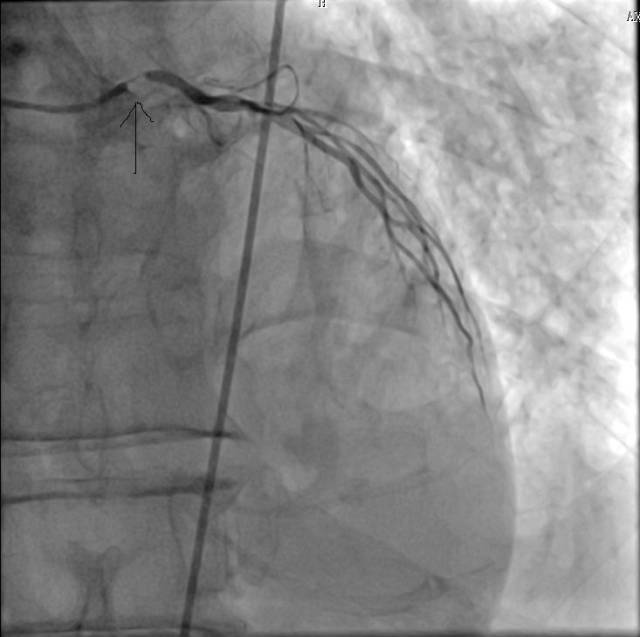

IABP

李某,男,63岁,急性前壁心梗死 合并室间隔穿孔,心力衰竭,应用 IABP支持

李某,男,63岁,急性前壁心肌梗 死合并室间隔穿孔,心源性休克,应 用IABP救治成功